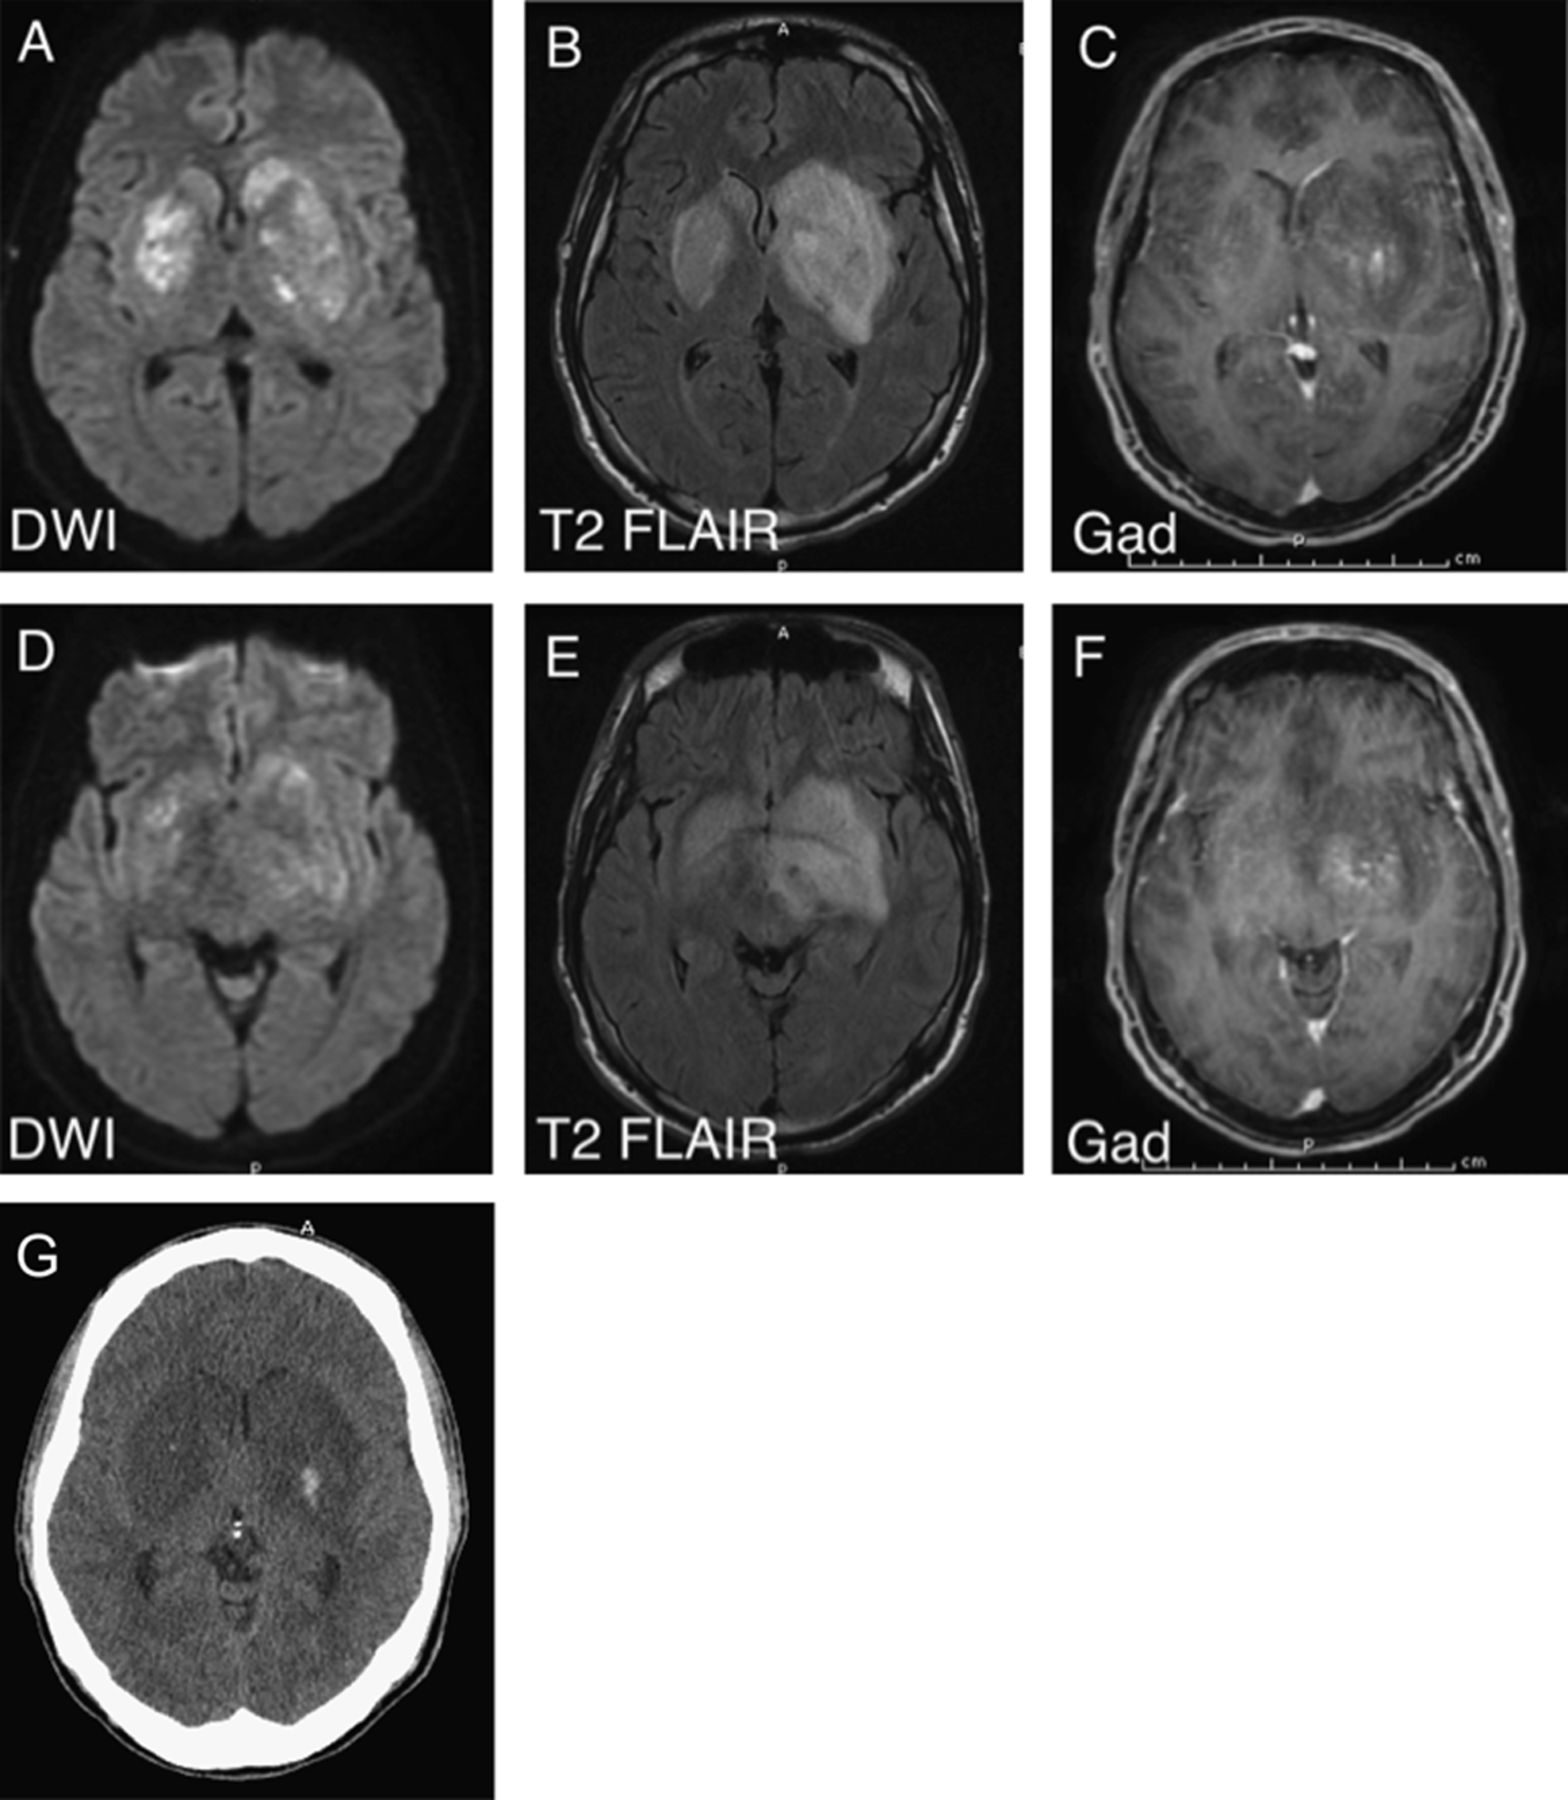

病人的精神状态在急诊科迅速恶化。他无法保护他的气管,气管插管,以确保足够的通风。最初的实验室研究非同凡响的白细胞计数21800 /毫米3(80%分段形式)和钠水平的128更易/ L。头部的CT扫描显示4.2厘米hypodensity左基底神经节的在该地区与当地质量效应和脑室系统的抹杀。苯二氮和大麻类毒理学屏幕上是积极的。血培养结果,艾滋病毒测试,快速血浆反应素,coccidiomycosis血清和脑脊液浓度是负的。CSF分析显示葡萄糖57 mg / dL,蛋白质111 mg / dL,白细胞计数400 /188金宝慱官网下载毫米3有67%的淋巴细胞和红细胞计数77000 /毫米3(痛苦的)。革兰氏染色剂,细菌和真菌培养,病毒pcr以及抗酸的细菌文化和脑脊液涂片全都是负面的。脑部核磁共振成像(图1中,一个显示限制扩散和基底神经节的T2 hyperintensity (L > R)与最小的对比度增强。T2信号异常也扩展到左侧颞区和左大脑脚、没有证明扩散限制。其他诊断测试期间执行病人的医院技术课程包括超声心动图显示正常射血分数没有任何瓣膜异常,和一个没有癫痫样的异常脑电图显示扩散慢。

(A) MRI diffusion-weighted成像(驾车)显示了在横向限制扩散基底神经节。(B) T2 fluid-attenuated反转恢复(天赋)显示vasogenic和双边基底神经节细胞毒性水肿。(C) T1 postcontrast图像显示最小增强左基底神经节。(D, E, F)相应的醉酒驾车,T2和T1 postcontrast序列在中脑的水平。(G) CT扫描显示出血性转化的双边基底神经节病变住院第三天。